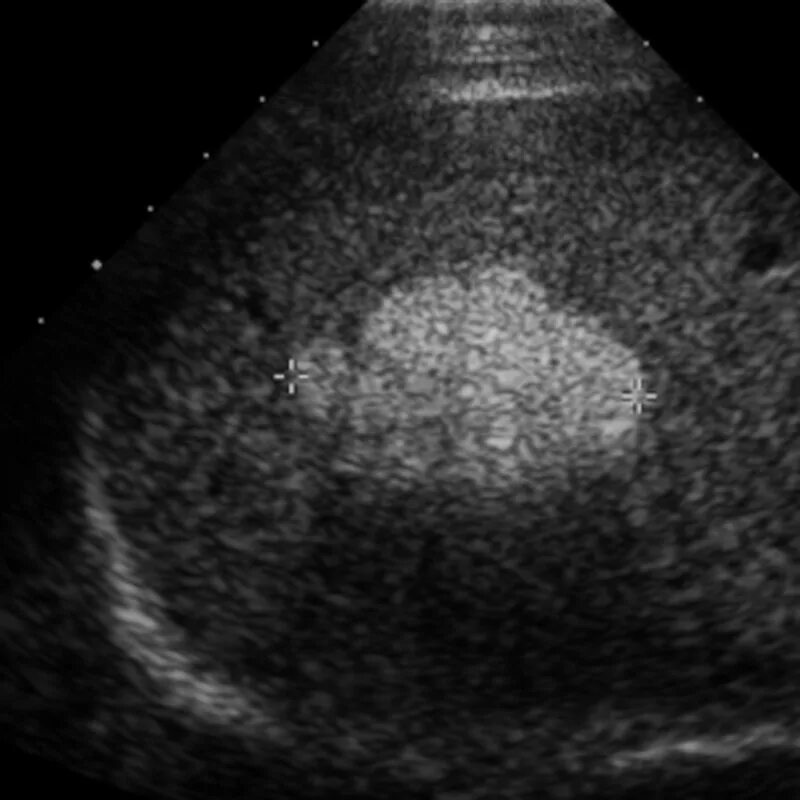

Диффузные изменения почек